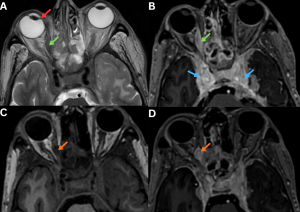

Fig 5: Clinical history:

A 48-year-old male with invasive sinonasal mucormycosis presented with acute right-sided medial deviation of the globe and worsening periocular pain.

Figure A:

Axial T2-weighted MRI image demonstrates mucosal thickening within the bilateral ethmoid air cells along with enlargement of the right medial rectus muscle (green arrow), resulting in medial deviation of the right globe (red arrows).

Figure B:

Axial post-contrast T1-weighted MRI image demonstrates intense enhancement of the right medial rectus muscle (green arrow) with extension toward and encasement of the cavernous sinus regions (blue arrows). Both internal carotid arteries show preserved contrast opacification.

Figures C & D:

Axial pre- and post-contrast T1-weighted MRI images demonstrate a well-defined T1 hypointense lesion within the left medial rectus muscle, showing post-contrast enhancement (orange arrows), compatible with early fungal infiltration.